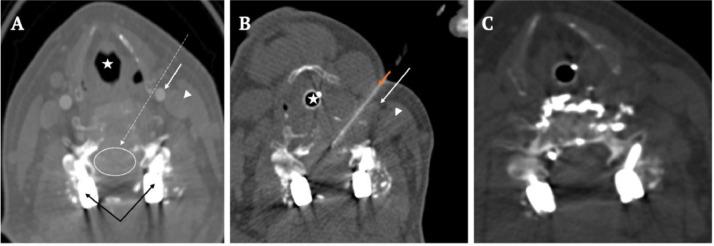

Symptomatic vascular spinal metastases will benefit from pre-operative tumor embolization - percutaneous with or without adjunct endovascular embolization. However, when a transpedicular approach is not feasible, an anterolateral approach may be a viable alternative. The authors report a 57-year-old woman with prior C3-T1 instrumentation who presented with acute cord compression from a pathologic C5 vertebral body fracture related to metastatic renal cell carcinoma. The patient underwent CT-guided direct tumor embolization with 33% n-butyl-2-cyanoacrylate via an anterolateral approach, followed by C5-corpectomy and anterior cervical C4-C6 fusion and plating with minimal blood loss (est. 20 cc) and a stable neurological exam post-operatively. In patients with highly vascular cervical metastatic disease who lack a viable transpedicular approach for preoperative tumor embolization, a CT-guided anterolateral approach is a viable alternative.

有症状的脊柱血管性转移瘤将受益于术前肿瘤栓塞——经皮栓塞,可联合或不联合血管内辅助栓塞。然而,当经椎弓根入路不可行时,前外侧入路可能是一种可行的替代方法。作者报告了一名57岁女性,既往有C3 - T1内固定,因转移性肾细胞癌导致C5椎体病理性骨折,出现急性脊髓压迫。患者通过前外侧入路,在CT引导下用33%的正丁基-2-氰基丙烯酸酯进行直接肿瘤栓塞,随后行C5椎体次全切除、颈前路C4 - C6融合及钢板固定,术中失血极少(估计20毫升),术后神经功能检查稳定。对于高度血管化的颈椎转移性疾病患者,若缺乏可行的经椎弓根术前肿瘤栓塞入路,CT引导下的前外侧入路是一种可行的替代方法。